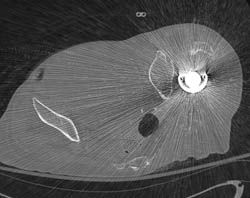

Metatarsal Fractures